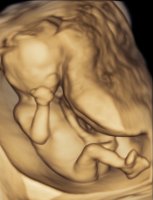

Tvilling 2 øverst, som er en jente, og tvilling 1 nederst som er litt usikker, men så mest ut som jente visstnok. :love7 Friske og aktive:Heartbigred 13+3.